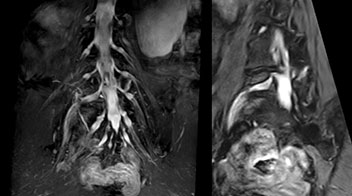

“In such case, we would then browse through axial T2-weighted MR images slice by slice and mentally reconstruct the actual situation based on both radiculography and MRI. Fortunately, NerveVIEW can now very well show nerve courses and presence of nerve compression or edema in one single image series.” “We have often seen NerveVIEW directly depict details of the nerve compression that were not observed by radiculography. Therefore, we think that with NerveVIEW we can reduce the number of invasive examinations, especially for some patients with lumbar plexus symptoms.”

The key concept in MR neurography, Dr. Yabuki stresses, is the ability to directly visualize spinal nerves, versus inferring the presence of pathology indirectly. “Before NerveVIEW, we estimated compression of the nerve by looking for the presence or absence of fat signal on other MR images,” he says.

“For example, in sagittal images, when the presence of fat is observed in the intervertebral foramen, it suggests that there is a margin around the nerve. Similarly, the absence of fat indicates that the nerve is being compressed. So, we used to deduce nerve compression indirectly. With NerveVIEW, however, we can observe the condition of the nerves directly, regardless of the presence or absence of fat. We always prefer such direct observation of anatomy over having to make an inference about it.”

“Although symptoms of typical disc herniation and atypical hernia are very similar, the actual site of herniation is different. It is therefore important to characterize the nerve’s condition both inside and outside of the intervertebral foramina. “Conversely, if we see no abnormality in NerveVIEW, we can assume at least that there is no severe condition that requires surgery. Like this, it can help us avoid unnecessary surgery. NerveVIEW can have a tremendous impact in this way.”